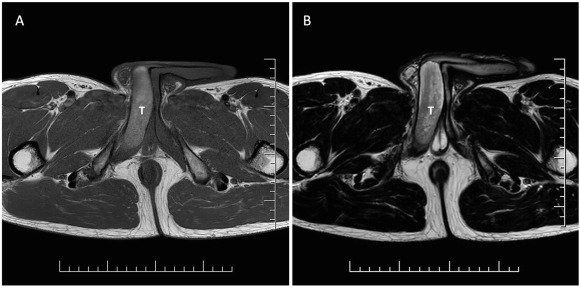

Exames de imagem revelam a zona do pênis atingida pela trombose, marcada com um T, e a ereção em tom mais claro